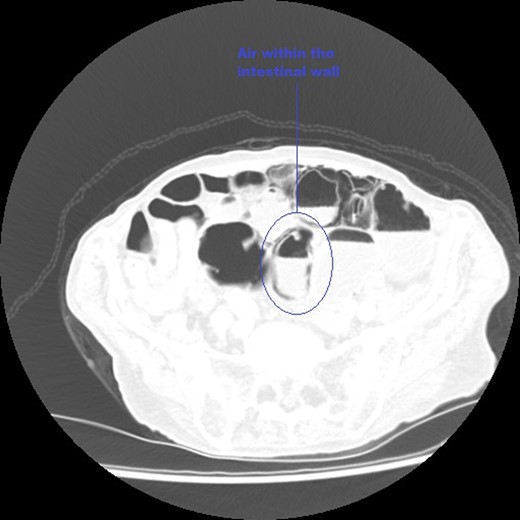

An axial CT image of the abdomen taken at initial presentation, demonstrating PI marked on the image.